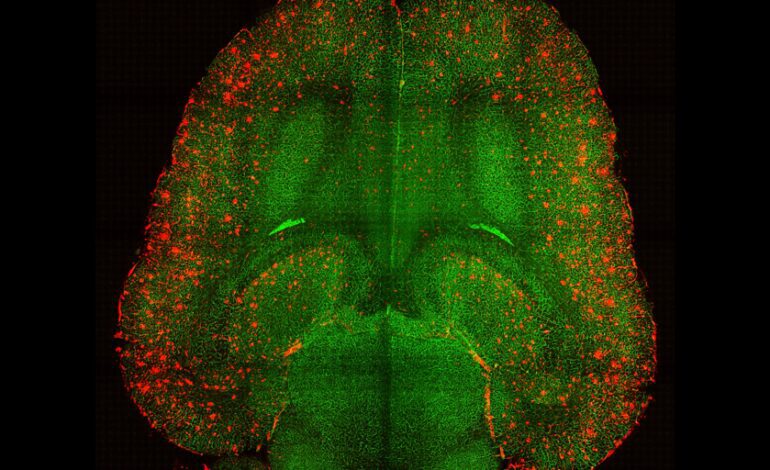

Para comprender este proceso, los investigadores analizaron el cerebro de roedores y realizaron experimentos en los que una señal, como un sonido corto, advertía de una recompensa (un trozo de azúcar). Observaron que los cambios en KCC2 alteraban la actividad de las neuronas dopaminérgicas..